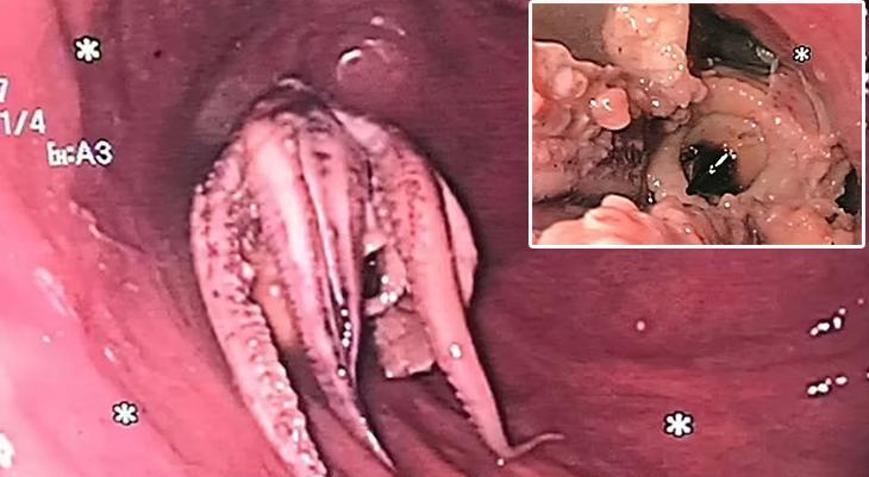

Singapur'da kusma şikayetiyle hastaneye giden bir adamın nefes borusunu inceleyen doktorlar gözlerine inanamadı. Söz konusu o kare dünya basınında manşet oldu.

Son günlerin en ilginç olaylarından biri gün içerisinde Singapur'dan geldi. Söz konusu olayın fotoğrafı mide bulandırırken detaylar pes dedirtti. Deniz ürünlerinin popüler olduğu ülkede 55 yaşındaki adam bir ahtapot yedikten sonra hastanelik oldu. Nefes güçlüğü ve yutkunma sorunu çektiği belirtilen adam apar topar tedaviye alındı. Doktorlar yaptıkları incelemelerde gördüklerini ise yerel basınla paylaştı.

Söz konusu o paylaşıma ahtapotun adamın boğazında sıkıştığı görüldü. Adı açıklanmayan hasta sağlık görevlilerine deniz ürünleri yemeğini yedikten hemen sonra kusmaya başladığını söyledi.

ENDOSKOPİYE ALINDI

Singapur'daki Tan Tock Seng Hastanesi'ndeki sağlık uzmanları, hastanın yemek borusuna küçük bir operasyon yaptı ancak başarısız oldu. Daha sonra endoskopi yöntemi ile ahtapot mide tarafında yönlendirildi ve buradan dışarıya çıkartıldı. Hasta, işlemden sonra 2 gün hastanede tutuldu daha sonra ise taburcu edildi.

Görüntülerin 2018'de çekildiğini belirten sağlık ekipleri o dönemde hastanedeki çalışmalarında sık sık benzer vakalarla karşılaştıklarını aktardı. Bir uzman ise konuyla ilgili 'Vakaların yüzde 10 ila 20'sinde endoskopik tedaviye ihtiyaç duyulurken, yüzde 1'den azı ameliyat gerektirir' değerlendirmesinde bulundu.